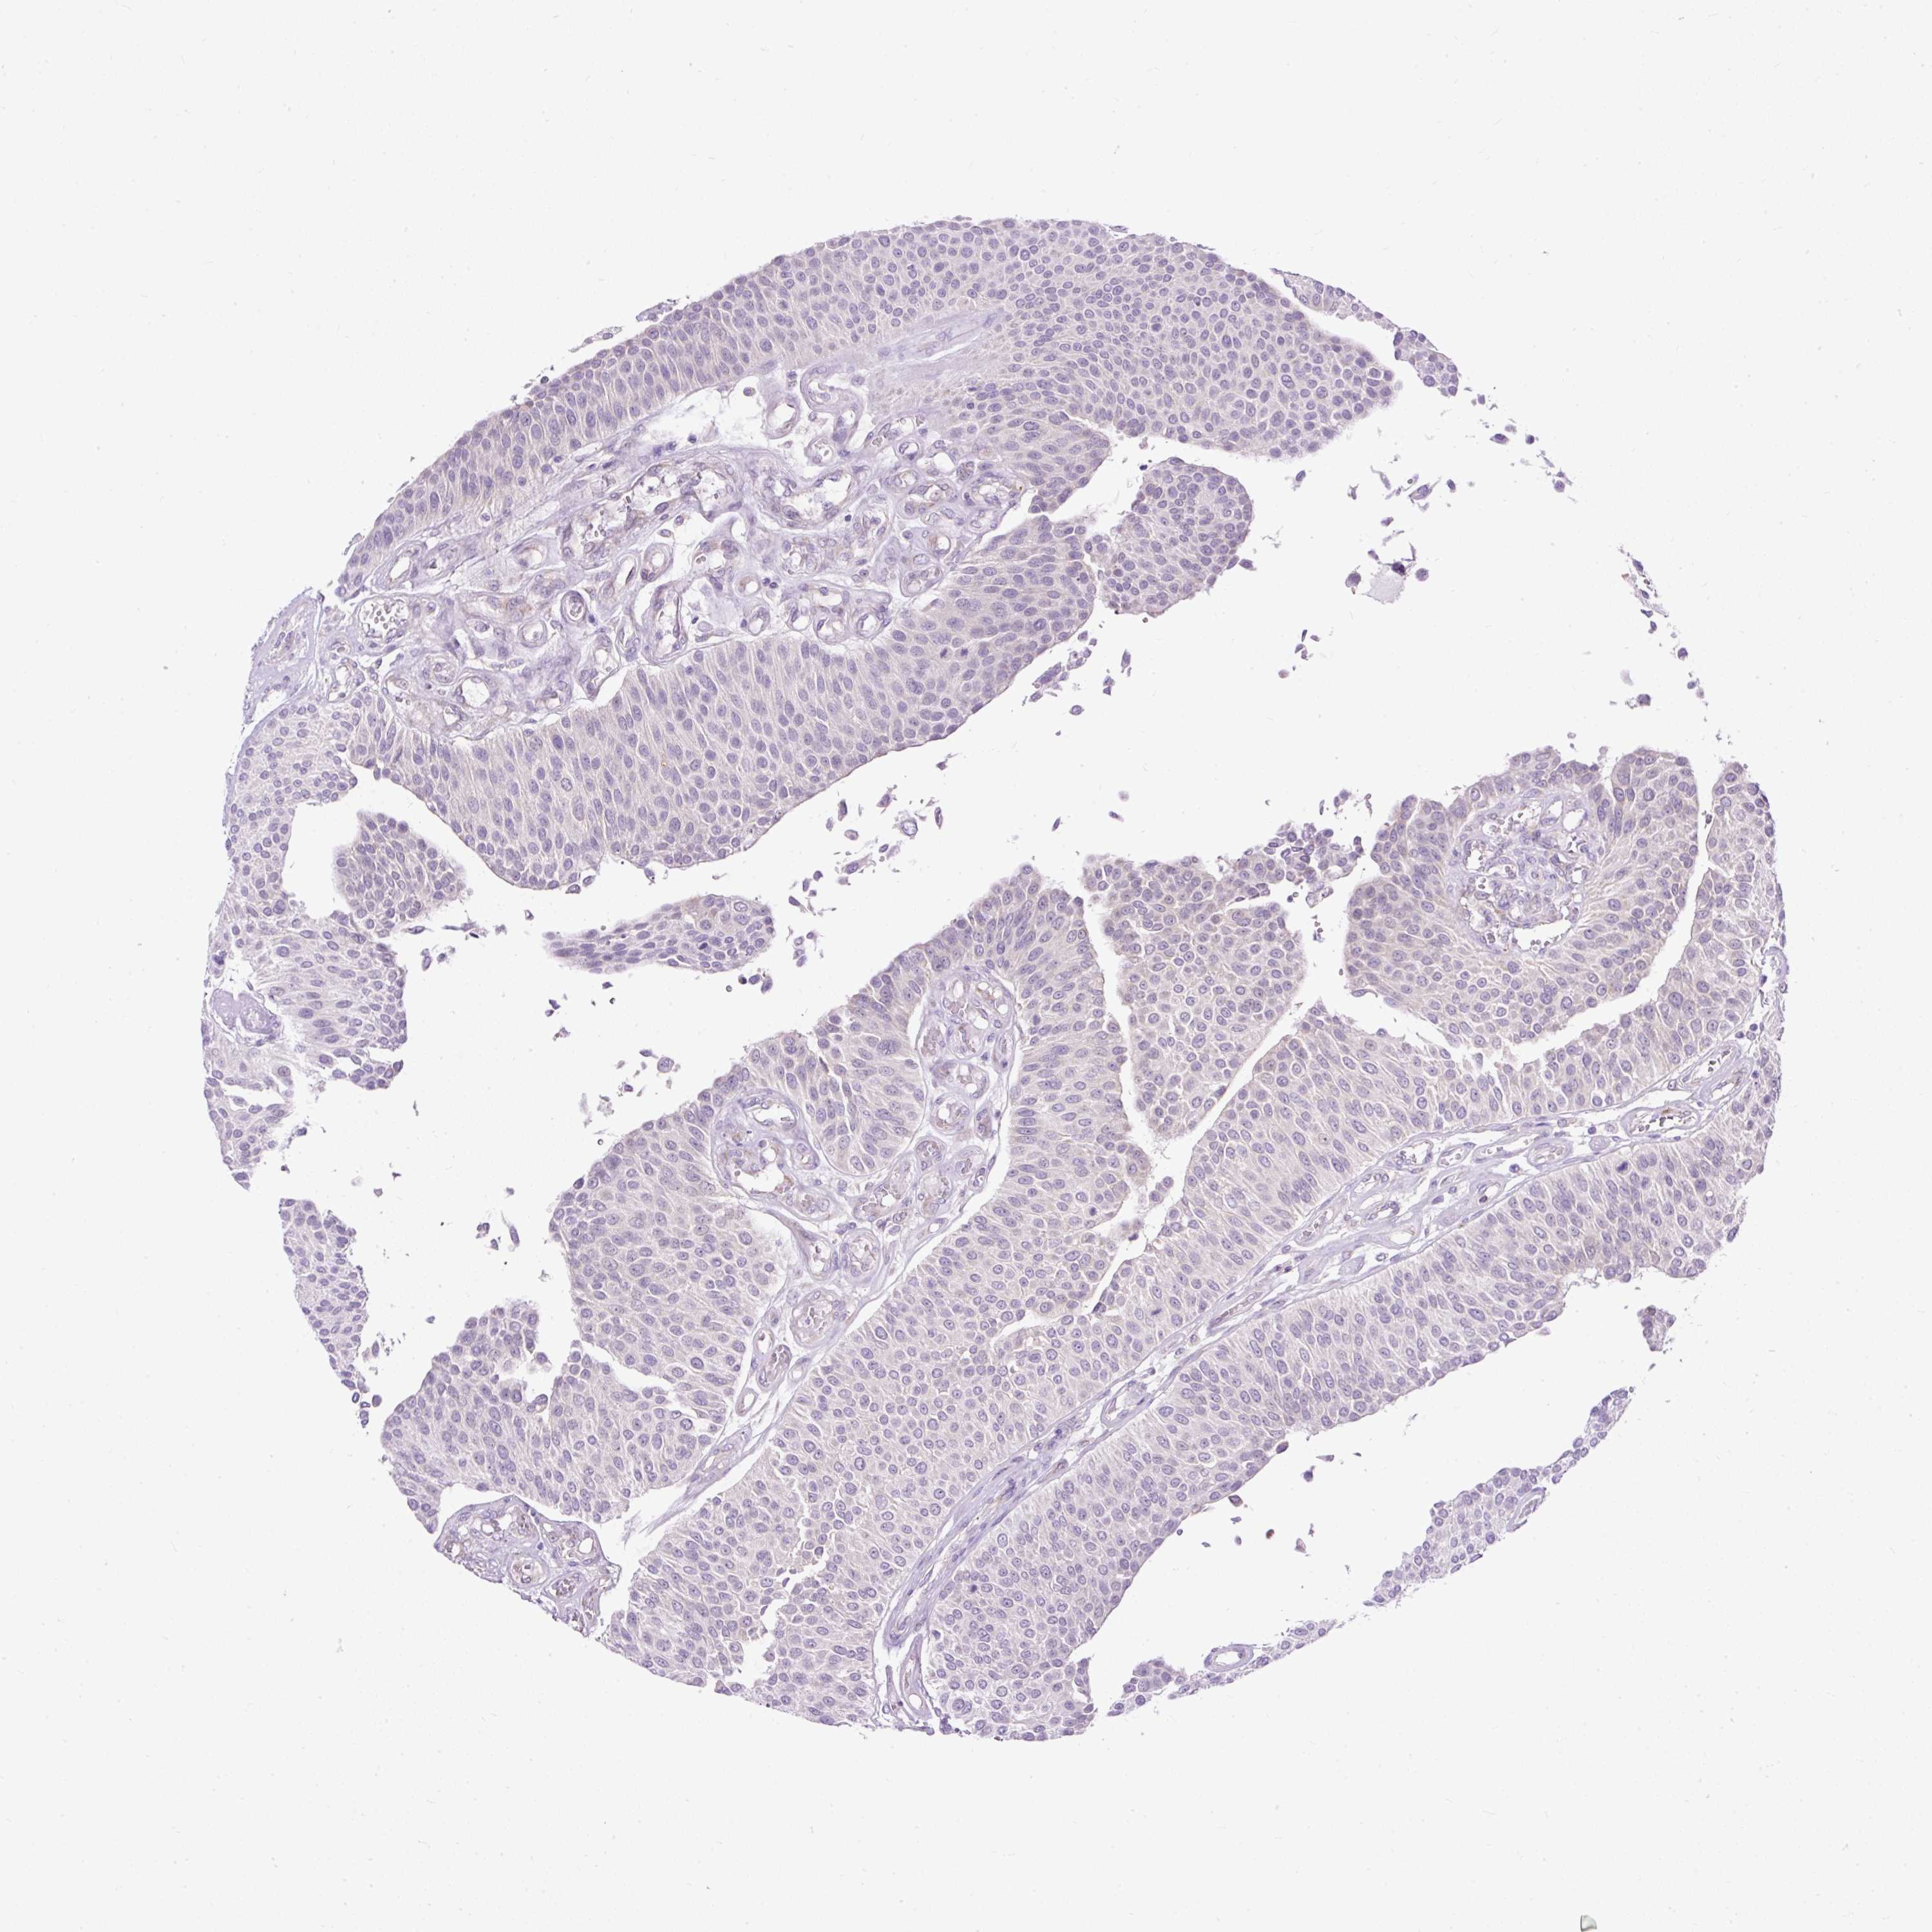

UROTHELIAL CANCER - Protein expressioni

A mouse-over function shows sample information and annotation data. Click on an image to view it in a full screen mode. Samples can be filtered based on level of antibody staining by selecting one or several of the following categories: high, medium, low and not detected. The assay and annotation is described here.

Note that samples used for immunohistochemistry by the Human Protein Atlas do not correspond to samples in the TCGA dataset.

Antibody stainingi

Antibody staining in the annotated cell types in the current human tissue is reported as not detected, low, medium, or high, based on conventional immunohistochemistry profiling in selected tissues. This score is based on the combination of the staining intensity and fraction of stained cells.

Each image is clickable and will lead to virtual microscopy that enables deeper exploration of all samples and also displays staining intensity scores, fraction scores and subcellular localization as well as patient and tissue information for each sample.

Antibody HPA045663

Antibody HPA051631

Urothelial carcinoma, High grade

Urothelial carcinoma, NOS

Urothelial carcinoma, Low grade